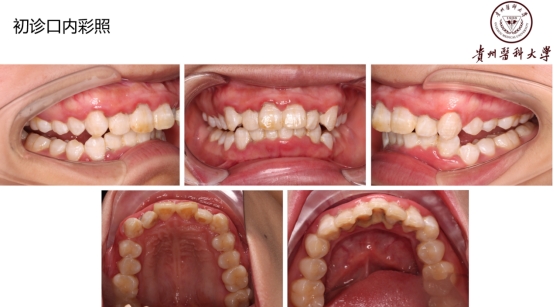

18岁,男性,经常抽烟,熬夜打游戏!!!

好发人群以及典型症状:该病好发于青壮年,多见于男性吸烟者、经常熬夜者、精神压力大者。得了这个病的话,前面描述的症状都可能会发生!牙龈的边缘及牙龈乳头发生坏死,常有黄白色假膜覆盖,很痛,有腐败臭味!!但是有这些症状时还是要小心另外一些很严重的疾病哦,比如白血病、艾滋等,得排除了它们,才能放心点。